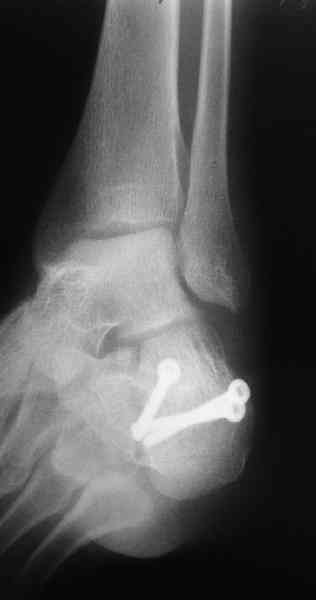

Re: Перелом пяточной кости

Пяточной пластиной

Открытый и закрытый способы лечения.